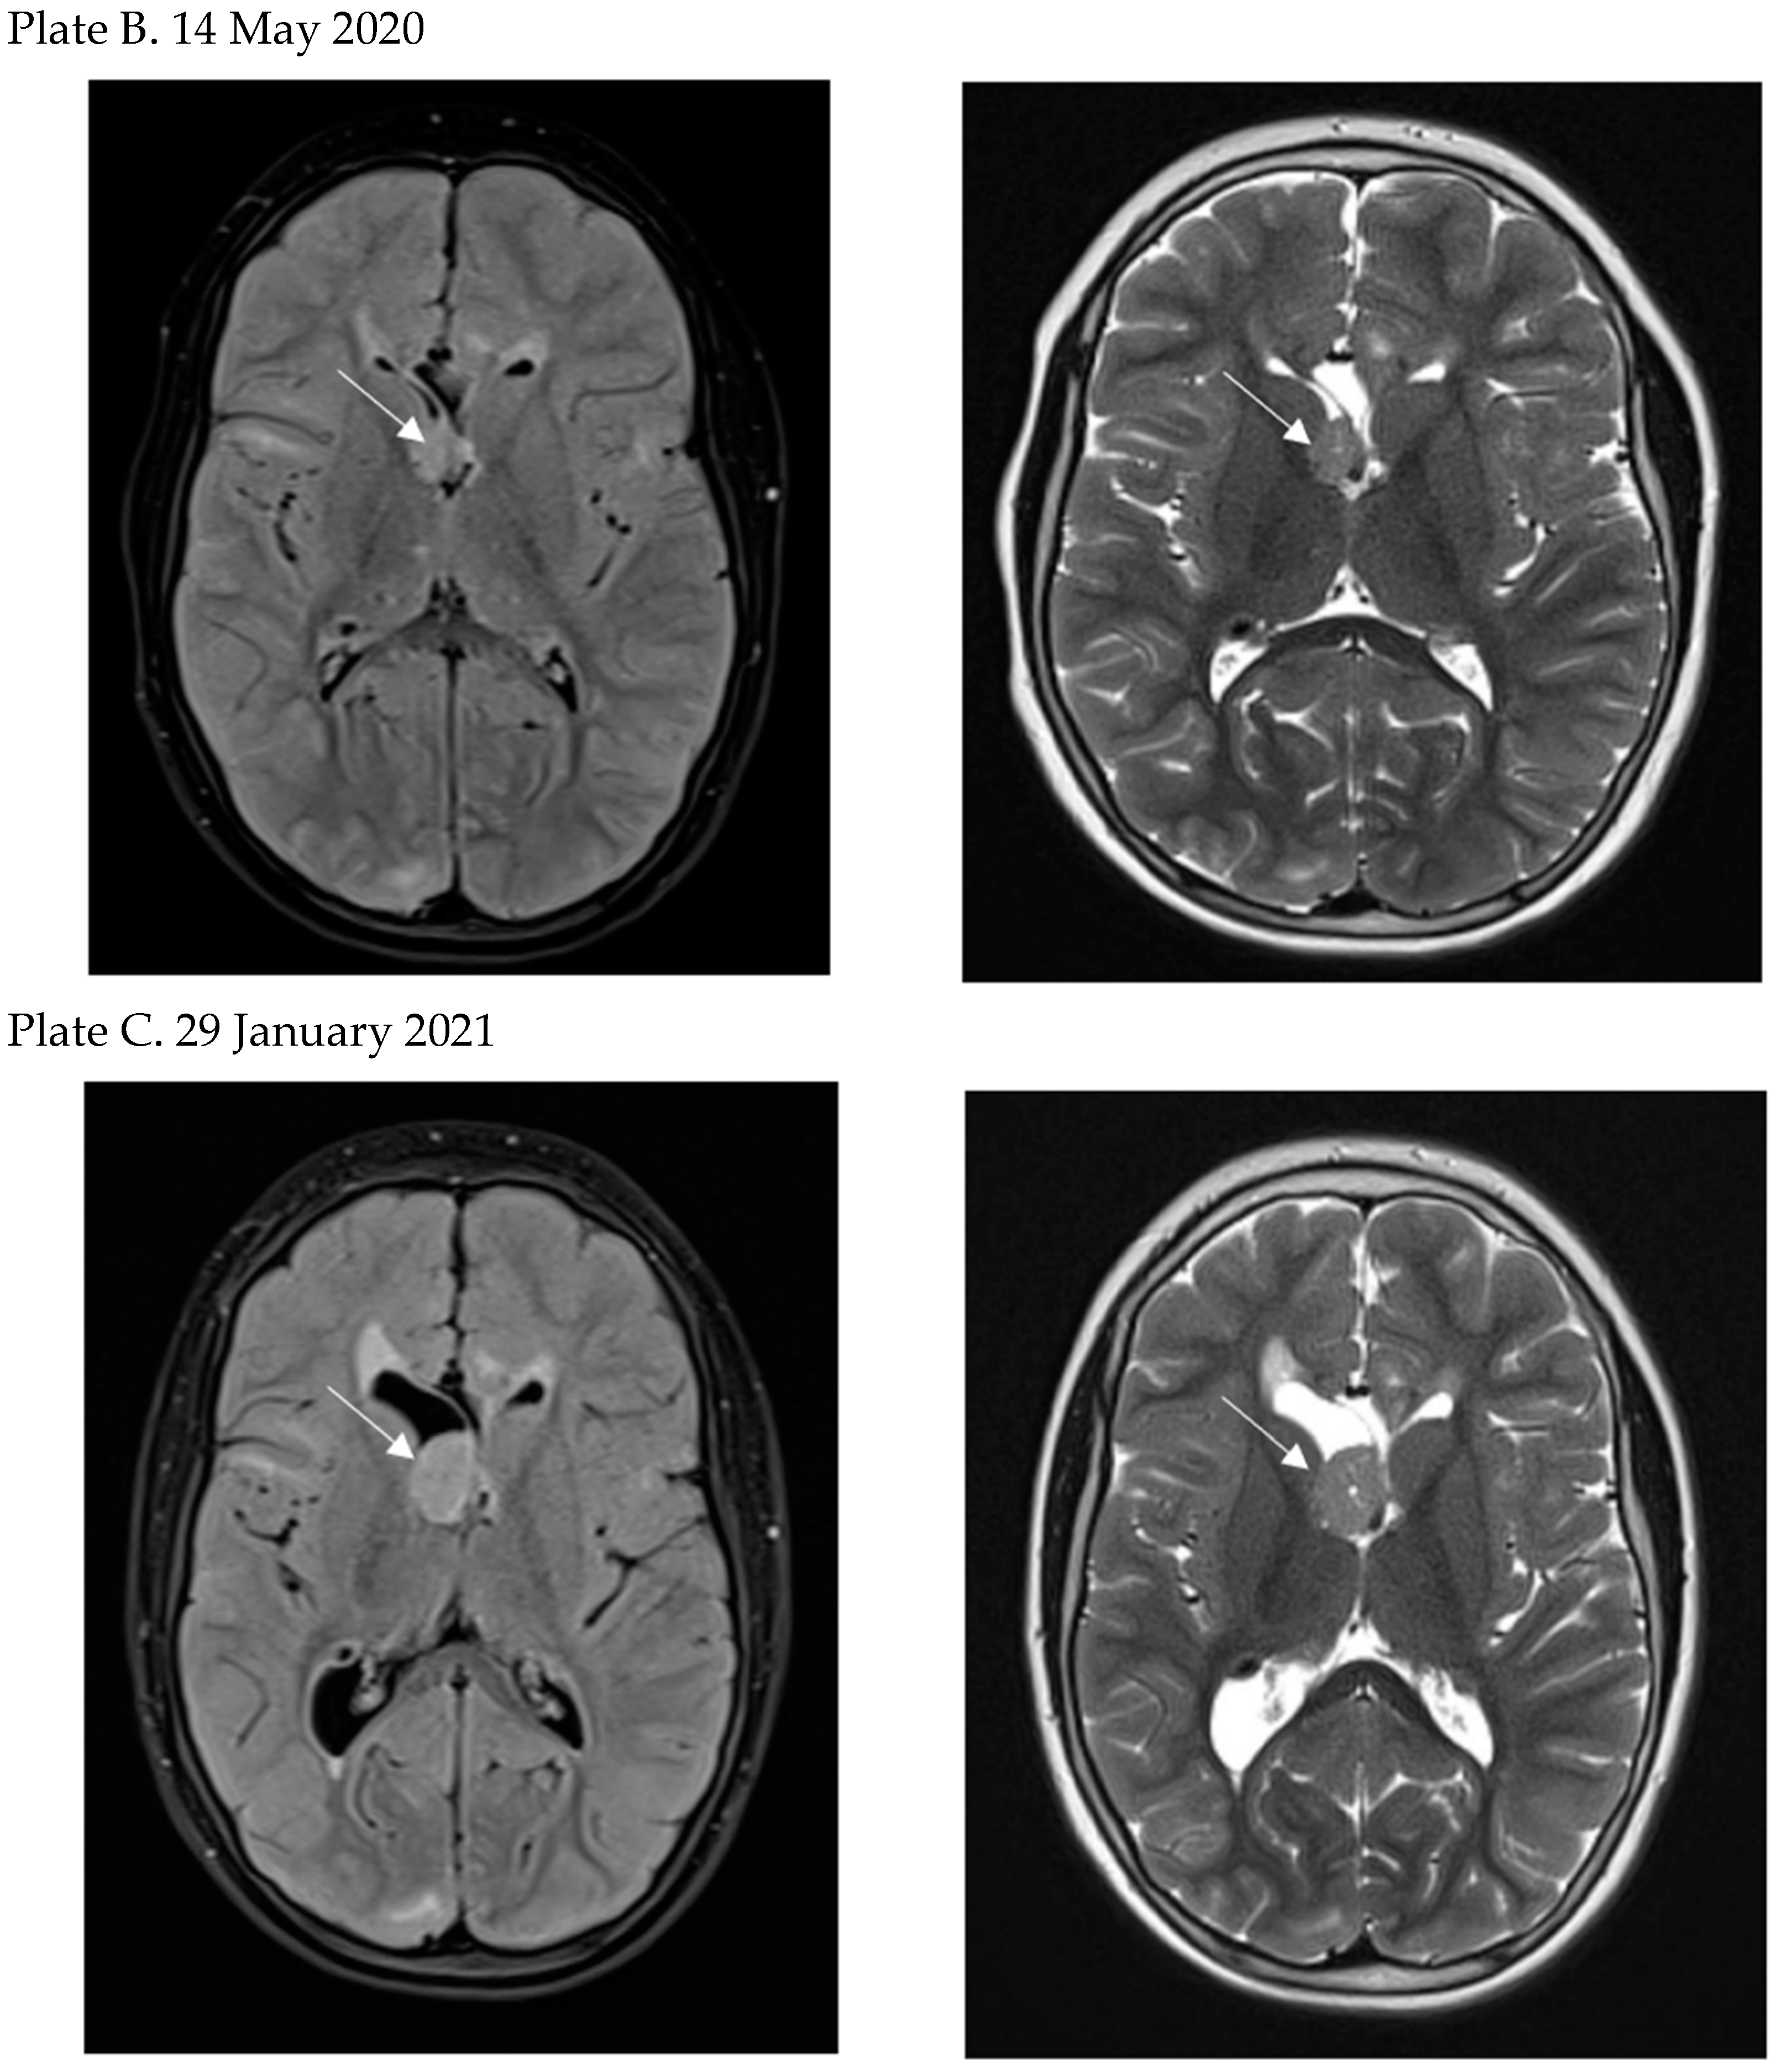

- Perek-Polnik, M.; Jozwiak, S.; Jurkiewicz, E.; Perek, D.; Kotulska, K. Effective everolimus treatment of inoperable, life-threatening subependymal giant cell astrocytoma and intractable epilepsy in a patient with tuberous sclerosis complex. Eur. J. Paediatr. Neurol. 2012, 16, 83–85. [Google Scholar] [CrossRef] [PubMed]